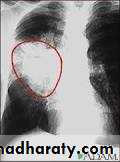

Common radiological presentations of bronchial carcinoma

*Unilateral hilar enlargement*Peripheral pulmonary opacity

*Lung, lobe or segmental collapse *Pleural effusion

*Broadening of mediastinum, enlarged cardiac *shadow, elevation of a hemidiaphragm

*Rib destruction